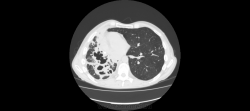

Здравствуйте, уважаемые коллеги! Меня зовут Владимир, работаю рентгенологом в ПТД, с недавнего времени осваиваю КТ. Хочу спросить вашего мнения по исследованию.

Больной наблюдается в ПТД с 2008го года. МБТ+ ни разу не было. На данный момент на фоне не специфической терапии отмечается снижение температуры, соэ остается высоким (60). Данные рентгенархива, к сожалению опубликовать не могу-нет фотоаппарата. Поэтому выкладываю сканы и видео.

Правое легкое уменьшено в объеме - значит есть фиброз, имеются полости распада - значит есть каверноз. А вот есть ли туберкуллез. Нет ВК, и локализация не вполне типична - в нижней доле. Может другой, столь же агрессивный возбудитель; например, актиномиккоз. Тема для консультации в вышестоящем ЛПУ.

Да, "неправильный" какой-то туберкулез. При таком массивном поражении одного легкого второе оказывается практически здоровым? Во всяком случае, своим неКТшным взглядом явной патологии не нашел. К тому же отсутствие ВК, и это при таких "кавернах"? Надо искать что-то другое, во всяком случае исключать. На вскидку даже трудно предложить дифряд. Что-нибудь грибково-простейшее?

Можно даже предположить, что первично был вариант или аномалия развития легкого, что-то связанное с врожденными кистами, гипоплазией и прочим.

Огромное спасибо за комментарии! Мне почему-то тоже пришла мысль о порочно развитом легком и присоединившейся позже инфекции, переросшей во временами обостряющийся хронический процесс.

Т.е. с Вашей точки зрения, процесс больше тянет на неспецифический?